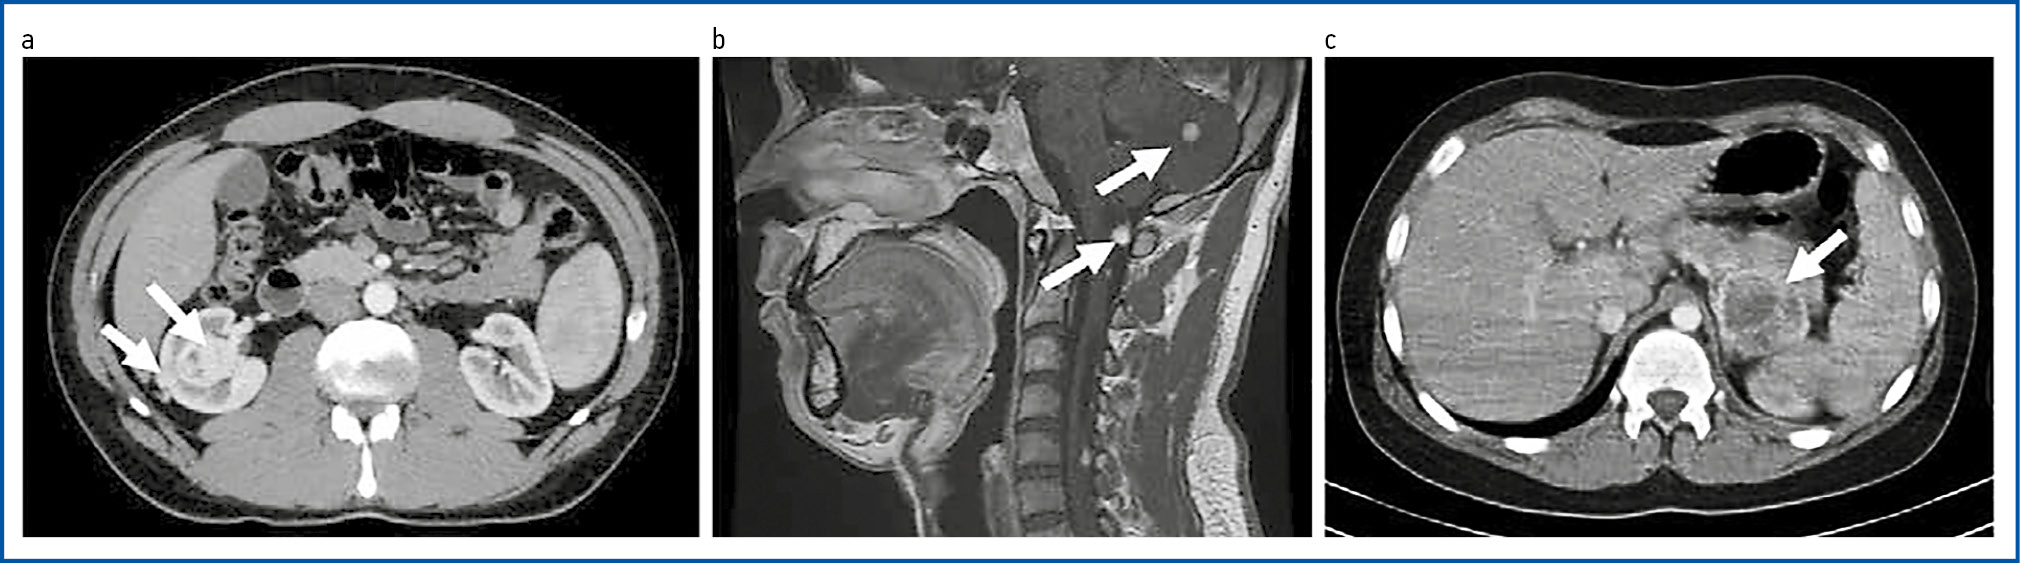

Рис. 1. Компьютерно-томографическая картина VHL-ассоциированных опухолей пациента Г. 28 лет: a – мультифокальные светлоклеточные почечно-клеточные карциномы правой почки (компьютерная томография, артериальная фаза); b – ГАБ мозжечка и продолговатого мозга (компьютерная томография); c – ФХЦ левого надпочечника (компьютерная томография, венозная фаза).

Fig. 1. Computed tomographic images of VHL-associated tumors of patient G., 28 years: a – multifocal clear cell renal cell carcinomas of the right kidney (computed tomography, arterial phase); b – cerebellar haemangioblastoma of the cerebellum and medulla oblongata (computed tomography); c – pheochromocytoma of the left adrenal gland (computed tomography, venous phase).